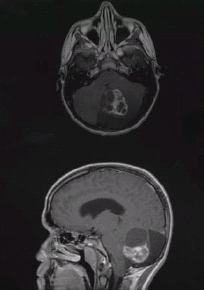

Grade II gliomas are a relatively uncommon malignancy, representing between 5% and 10% of brain tumors, said Jan C. Buckner, MD, of the Mayo Clinic, in Rochester, Minnesota. Though these are slow-growing tumors, Buckner said that “nearly all patients eventually develop neurological decline and premature death.”